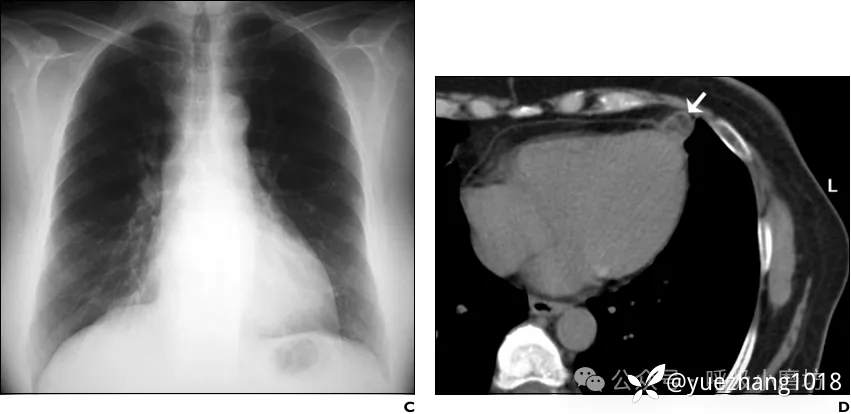

2个月后影像学随访证实心旁密度消失(图2C)。胸部CT显示脂肪病变及邻近心包增厚显著减小(图2D)。

图2C 2个月获得的随访胸部X线片显示心旁高密度影已消失;2D 随访CT显示心包外病灶体积显著缩小(箭头所示),相邻心包增厚已消失